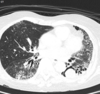

80 Mulher, Tosse

Consolidação com cavitação em lobo superior direito

Adenocarcinoma